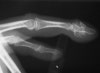

X-ray : 골연골종(Osteochondroma)

X-ray만으로도 쉽게 진단할 수 있습니다.